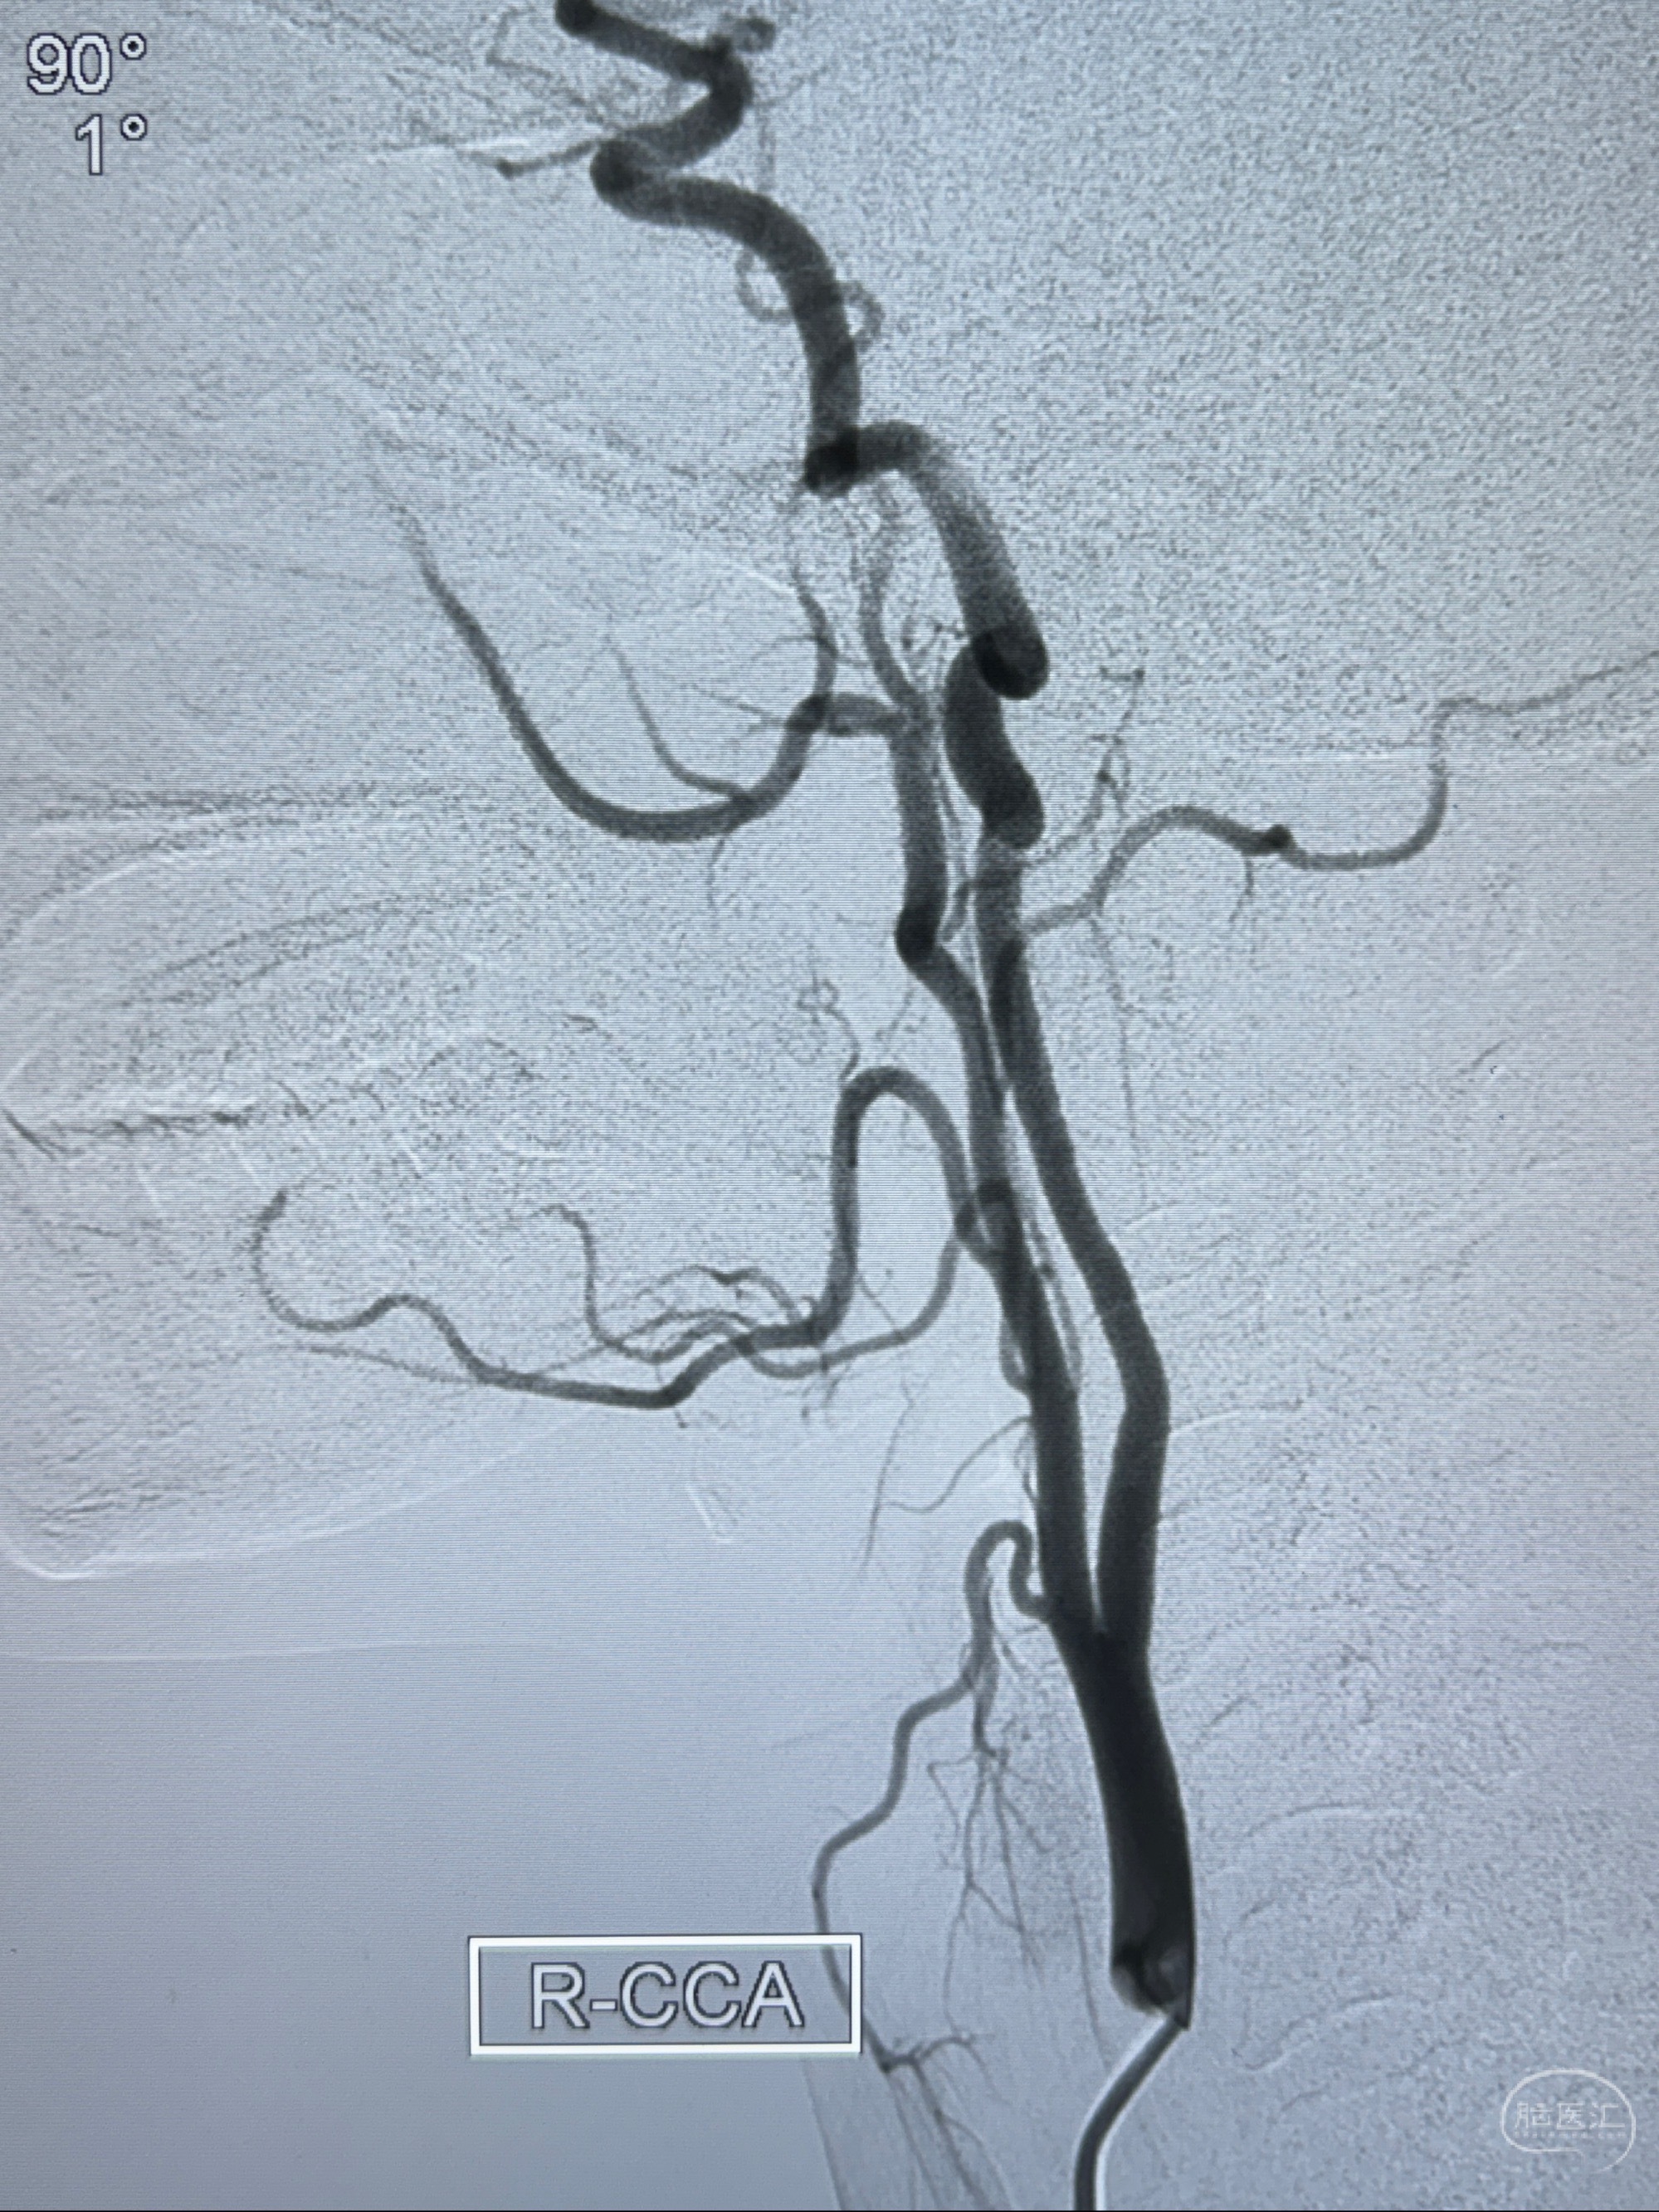

2023-11-03 蓝十字脑科医院 头颅CTA:左侧颈内动脉C6段微小动脉瘤可能(约2mm),右侧大脑前动脉A1段纤细(对侧优势),左侧大脑中动脉提前分叉。

2023-11-13DSA:左侧颈内动脉眼动脉后壁动脉瘤